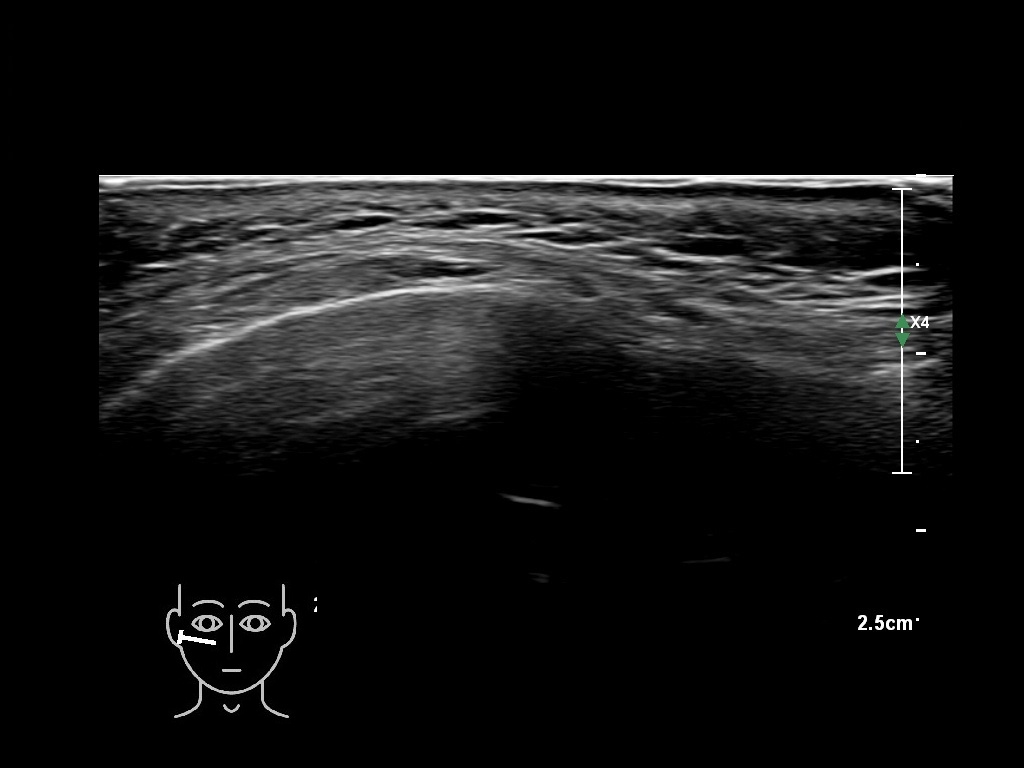

Draw in the image on the right where the fillers are located. To check if your answer is correct, please click on the secondary image.